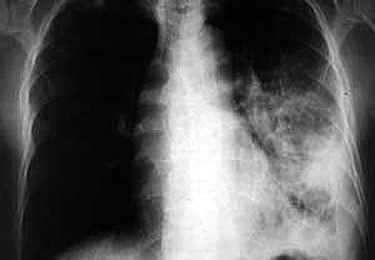

Londres, qui est la capitale ouest-européenne la plus touchée par la tuberculose, a mis en œuvre avec succès une unité mobile de dépistage par radiographie, qui se rend dans les communautés les plus à risque, selon une étude publiée dans le British Medical Journal et présentée à l’université de Warwick (centre) mercredi.

Le service se déplace dans les lieux où les populations les plus vulnérables à la maladie résident : services de traitement des drogués, centres d’accueil des personnes sans domicile fixe, etc.

Les personnes passent une radio, sur une base volontaire, et sont ensuite suivies de près par des équipes médicales pour le traitement, qui prend en général six mois. Un bon suivi du traitement est essentiel pour éviter le développement de souches résistantes du bacille.

Sur les 9.040 cas de tuberculose déclarés au Royaume Uni en 2009, 38% étaient localisés à Londres (3.440 cas).

Cette ville, qui accueille de nombreux immigrés de pays pauvres, a le taux le plus important de tuberculose des capitales ouest-européennes, avec une augmentation de 30% ces dix dernières années et un doublement des cas de tuberculose multirésistante entre 2005 et 2009.

Une étude faite en 2003 a montré que les SDF, drogués et prisonniers couraient un risque 10 à 30 fois plus élevé de contracter la tuberculose que l’ensemble de la population londonienne. Ils sont aussi les moins accessibles aux services médicaux.

L’unité mobile a permis de dépister 16 tuberculeux par an dans ces populations vulnérables depuis 2007, et de suivre dans leur traitement plus de 100 autres personnes chaque année.

“Londres a vu une résurgence de la tuberculose à une échelle inconnue dans les autres capitales ouest-européenne en vingt ans. Le nombre des nouveaux cas chaque année dans l’arrondissement de Brent (nord-ouest de Londres) est comparable à celui du district de Karonga au Malawi”, a souligné le principal auteur de l’étude, Ibrahim Abubakar.

“Cette unité à elle seule ne va pas renverser la tendance à Londres, mais elle peut avoir un impact sur cette population à haut risque, dans laquelle on sait que la transmission de la maladie est la plus importante”, a-t-il estimé.